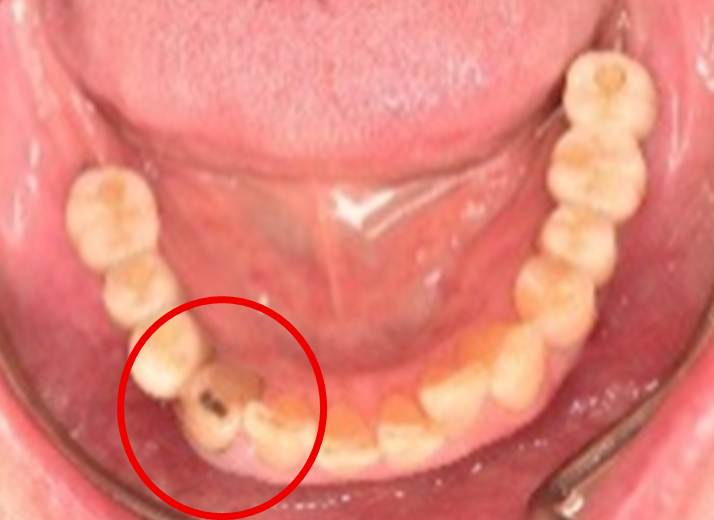

男性 Mさん 50代 (オールセラミック冠)

主訴

右上奥歯が、冷たいものにしみる。

治療内容

歯髄(神経および血管)まで到達する大きな虫歯でしたので、抜髄(歯髄を取り除く)をし、ファイバーコアをいれ、オールセラミック冠を被せました。

所感

現在、保険治療において、限定的ではありますが、大臼歯にも白い被せ物(プラスチック冠)ができるようになりました。しかし、実感としてプラスチック冠は、

- すり減りやすい。割れることがある。

- バイオフィルム(細菌およびそれから産生される副産物の塊)が付着しやすいので、歯周病および2次カリエス(被せ物と自分の歯の境目から再度虫歯になる)になるリスクが高い。

- 変色する。

という点を感じます。白い被せ物が保険の治療でできるという理由で、安易にプラスチック冠を選択し、割れたりすり減ったり、変色したらもう一度被せなおせばいいと考えるのであれば、一度立ち止まって考えてみてください。歯の量は、治療するたびに薄く少なくなり、歯根破折のリスクが高まります。もし大きな虫歯になってしまったら、最高レベルの根管治療をし、最良の被せ物であるオールセラミック冠を被せ、定期的にお口の中のクリーニングをし、同じ歯を2度と治療しないことが、歯を長持ちさせる最良の方法だと考えます。

オールセラミック冠(失活歯):¥104,500(税込)

Before

劣化したプラスチック冠

After